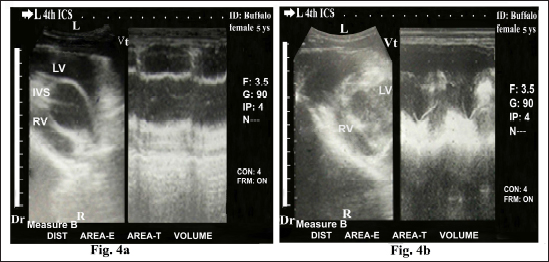

The heart was imaged from the left fourth ICS in midway between the elbow and shoulder points as the angle of the transducer directed dorsally and slightly cranially toward the third ICS, showing visualization of the right ventricular outflow tract (RVOT); RA, RV, TCV, PA, and pulmonary valve (PV) (Fig. 3). Cross sections at the apex of the heart, either in diastole (Fig. 4a) or systole status (Fig. 4b) showed RV and LV. Cross sections in the base of the heart showed RA, LA, TCV, and MV either in diastole (Fig. 5a) or systole status (Fig. 5b). Regular and strong myocardial contractility was clearly observed in both B-mode and m-mode 2-D-gray scale ultrasonography in all buffaloes.

Fig. 4. Echocardiogram of caudal long axis view in adult healthy female non-pregnant (5-year-old) buffalo (left side) during diastole (a) and systole (b) using a 3.5 MHz sector 2-D-gray scale transducer (B-mode and M-mode). It was imaged from the left fourth ICS in the midway between the elbow point and shoulder point. It showed CS in the apex of the healthy heart with regular, strong contractions and clear margins. The RV, LV, and IVS were clearly visualized. Dr; Dorsal. Vt; Ventral. R; Right. L; Left.